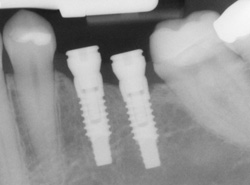

Single or Multiple Implants

Implants are versatile. If you are only missing one tooth, one implant plus one replacement tooth will do the trick. If you are missing several teeth in a row, a few strategically placed implants can support a permanent bridge (a set of replacement teeth). Similarly, if you have lost all of your teeth, a full bridge or full denture can be permanently fixed in your mouth with a strategic number of implants.